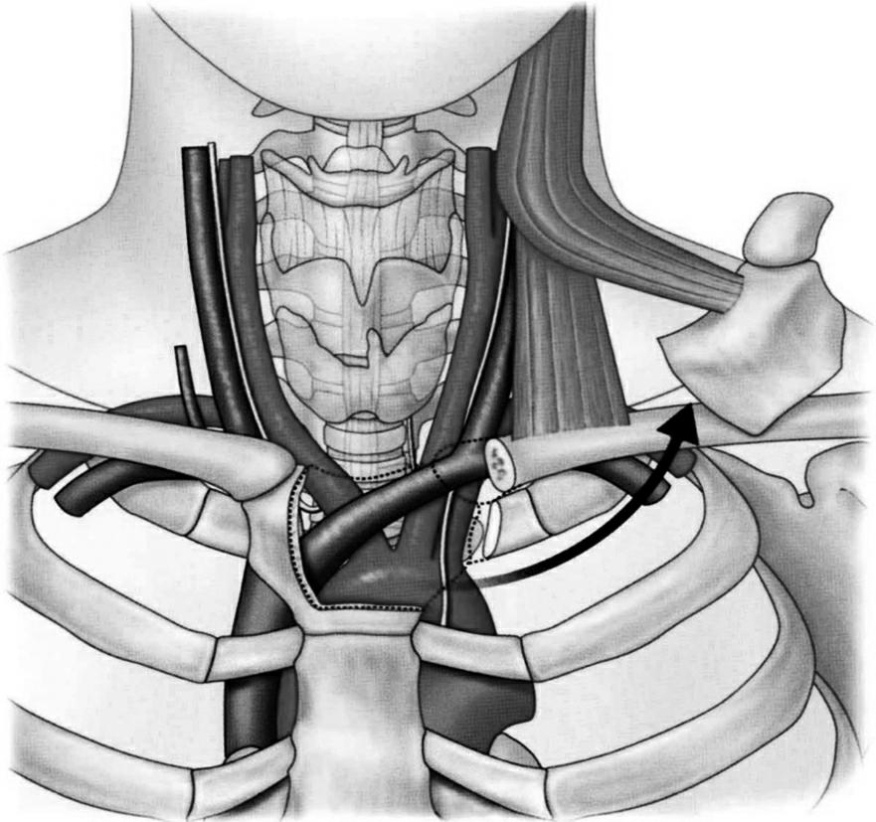

图4 经胸骨锁骨入路

切除胸骨柄和锁骨后显露锁骨下动脉、颈动脉鞘和气管

过程:依次切开皮肤、皮下组织及颈阔肌,游离颈阔肌,在胸锁乳突肌和舌骨下肌群间隙分离,切断肩胛舌骨肌,向两侧牵开颈动脉鞘及气管和食管,显露椎前筋膜。在骨附着点切断胸锁乳突肌的胸骨头和锁骨头,分离胸骨前方组织,显露胸骨柄,剥离胸骨舌骨肌、胸骨甲状肌的胸骨附着部,分离胸骨柄,并分离显露胸锁关节和锁骨内1/3段,切除胸锁关节、胸骨柄半侧、第一肋的胸骨端、第二肋软骨,显露上纵隔,沿C7椎前筋膜钝性往下分离,显露胸椎椎前筋膜。切开椎前筋膜,显露病变椎体及椎间隙,根据病变性质处理病变节段。然后将切除骨原位固定回植,依次缝合,闭合切口。